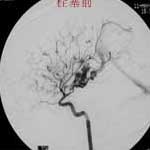

四.硬脑膜动静脉瘘(AVF)

----硬脑膜AVF是一种极复杂的颅内血管病,其分型方法可根据静脉引流的方式为:硬膜窦型、皮层静脉型、硬脑膜窦至皮层静脉型、硬膜下静脉湖型、脊髓静脉型。也可以根据瘘口发生部分为:海绵窦区,横窦乙状窦区、窦汇区、上矢状窦区、颅底区。栓塞治疗方法须根据分型而定,原则上是以永久性栓塞剂闭塞瘘口。单纯行瘘口孤立术,既创伤大,又难以彻底解决问题,一支支供血动脉的栓塞,则此起彼伏,诸多侧支循环,十分棘手。通过对引流静脉血液动力学分析,针对静脉窦的”竞争性血流”,可以采取静脉窦闭塞的方法,从根本上解决多发性瘘口,在这方面一系列的血液动力学、影像解剖学以及胚胎学的研究对治疗难治性脑膜动静脉瘘均有重要意义。